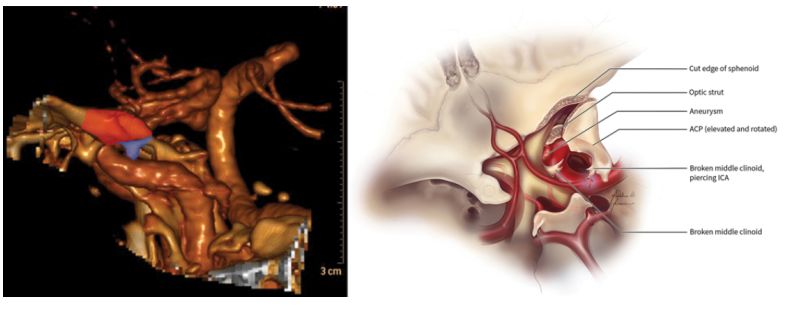

8.中床突及鞍旁区域的形态学测量分析

A morphometric survey of the parasellar region in more than 2700 skulls: emphasis on the middle clinoid process variants and implications in endoscopic and microsurgical approaches.

PMID: 28799880 DOI: 10.3171/2017.2.JNS162114

美国凯斯西储大学医学院的Sharma A等对2726例颅骨标本的鞍旁区域进行形态测量分析,包括观察中床突(middle clinoid process, MCP)是否存在,以及其尺寸、形态学分类、比邻结构,并根据年龄,性别和种族进行分类。研究认为,骨性MCP的变异可能是鞍旁手术中颈内动脉损伤的重大危险因素。

【郑 璇】